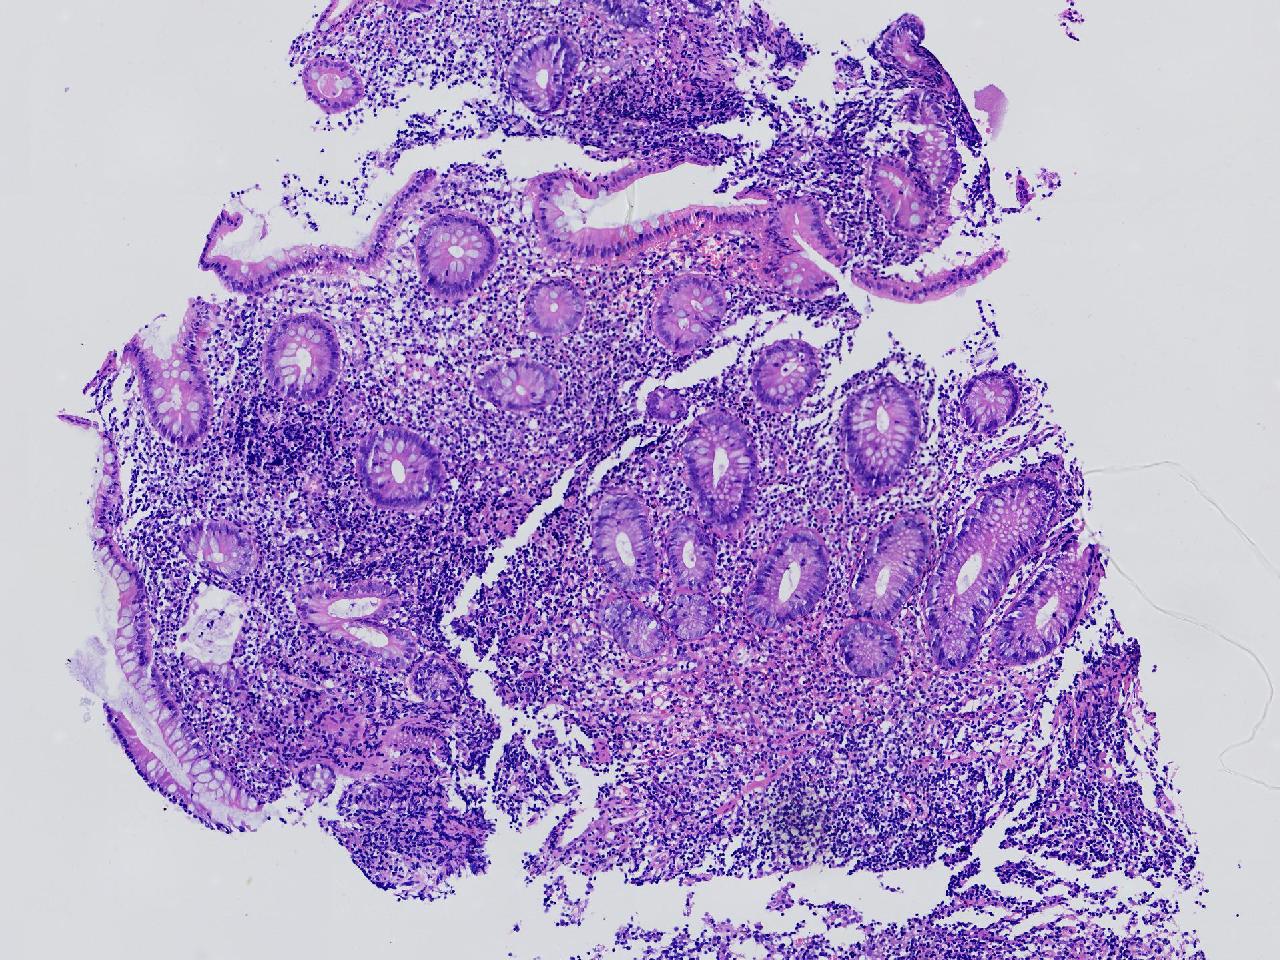

男,62岁,回盲部附近见多发片状溃疡,底覆薄白苔,周围粘膜充血水肿,活检2块,质软,弹性可。

回盲部活检

灰白色不整形软组织2块,直径均0.2厘米。

考虑:溃疡性结肠炎?

炎症性肠病要考虑,具体的类型不太好确定,需要结合临床。

上级医院会诊,不除外炎症性肠病,结合临床。